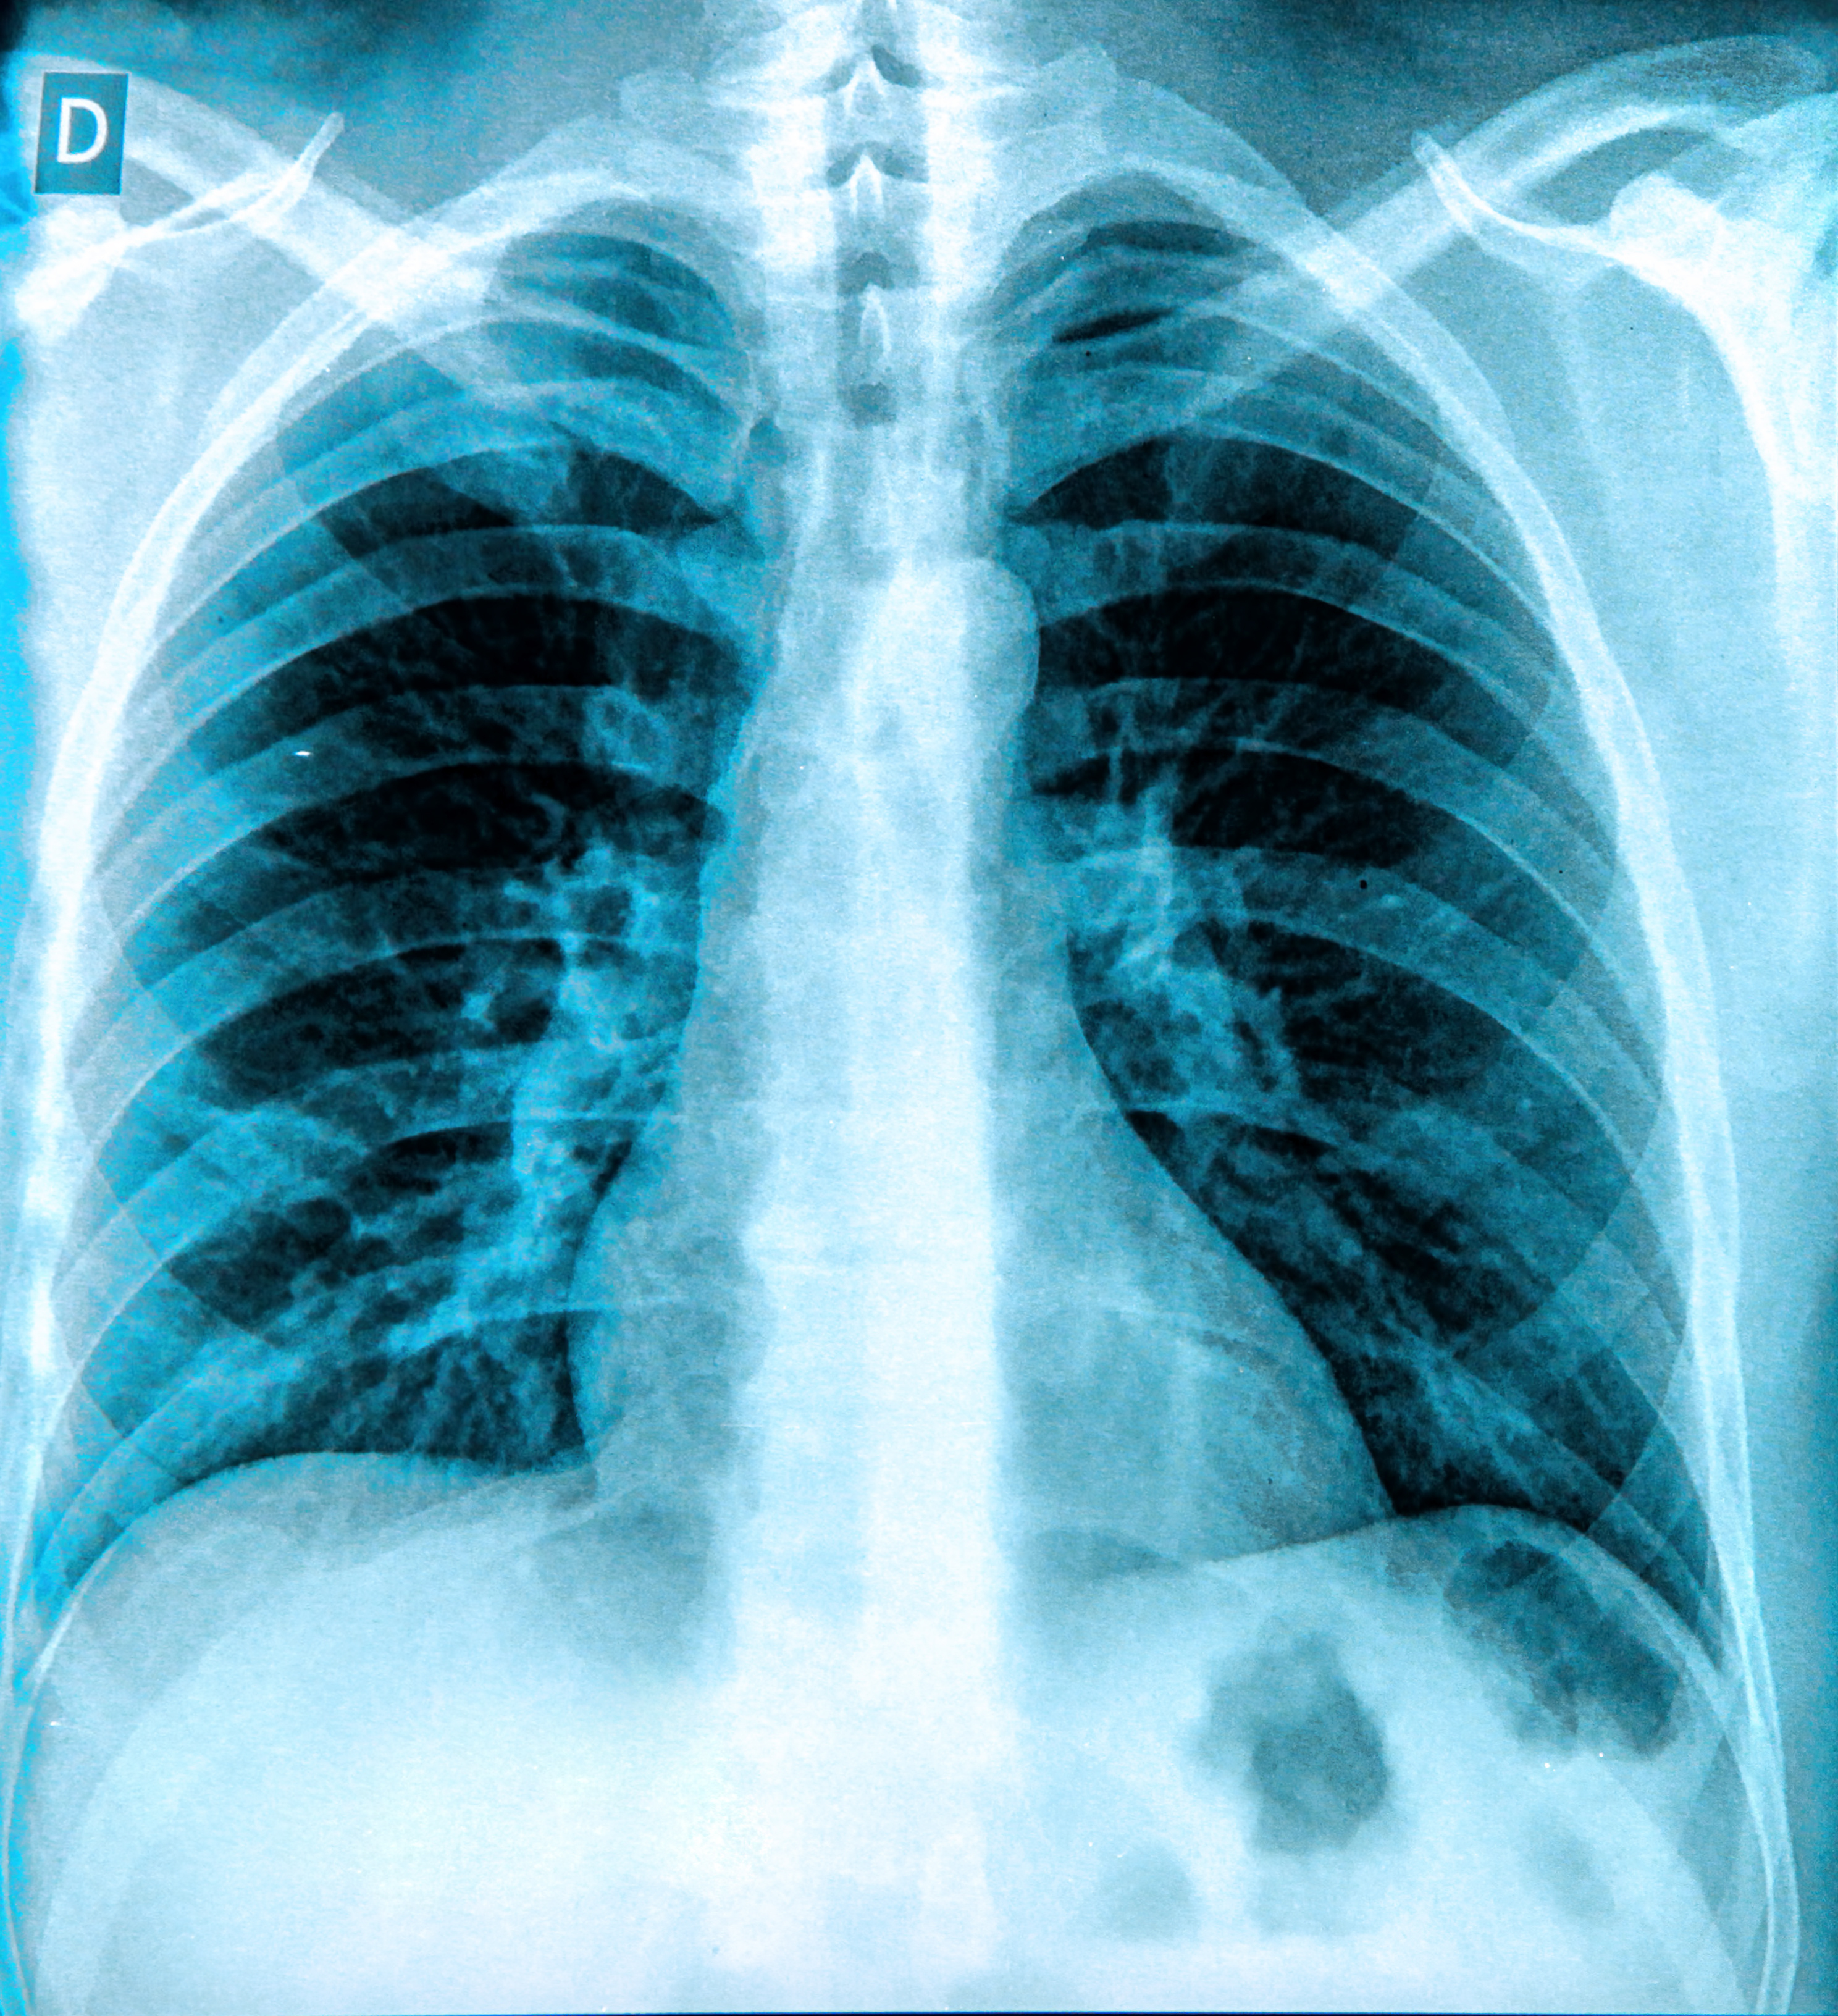

Aside from our ECR coverage, it appears that researchers are calling for more “real-world” studies of AI algorithms designed for interpreting chest x-rays. Recently, a group in Spain tested a product called ChestEye (approved in the European Union in 2019) and found it provided less than what’s required for clinical implementation.